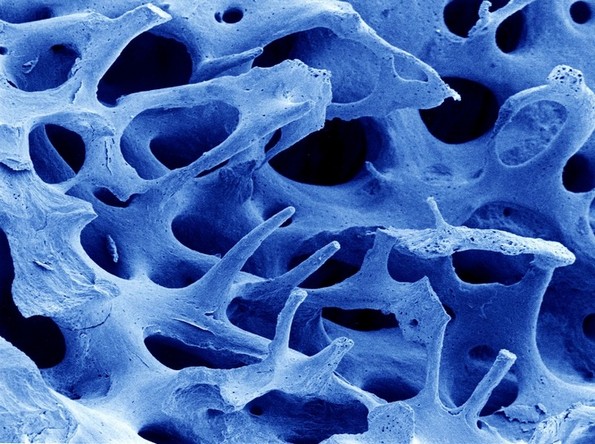

2. Коска